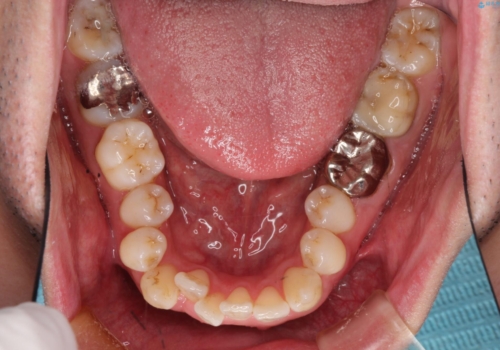

初診時の歯並びの状態としては、右上の犬歯がいわゆる八重歯の状態であり、強いガタガタが上下ともにある状態でした。

スペースの不足量が多く、抜歯を伴うワイヤー矯正にて治療を行いました。

若干の口元の突出感もあったため、抜歯によるスペースを利用し、がたつきの改善と前歯の後退をを行いました。